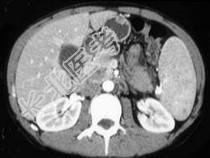

- 单项选择题女,56岁, 腹部胀痛不适、食欲减退,影像表现如下图, 最佳诊断是 ( )

A、胰腺转移癌

B、胰腺腺癌

C、胰腺假性囊肿

D、慢性胰腺炎

E、急性胰腺炎